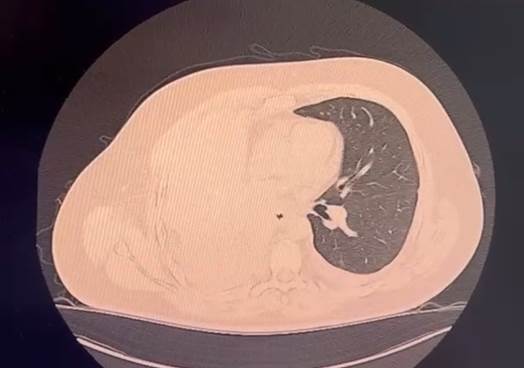

No dia 1/9/23, iniciou terapia de primeira linha com alectinibe 600 mg duas vezes ao dia, inicialmente adquirindo a medicação por meios próprios e depois após pleito judicial, visto que tal medicação não é custeada no serviço de saúde público brasileiro, sem apresentar quaisquer efeitos colaterais. Houve redução de 29% do CEA, voltando à faixa da normalidade com resultado de 4,73 em 6/12/23 e, em nova tomografia de 5/1/2024, houve grande resposta parcial, evidenciando pequeno derrame pleural à direita e redução de 89% no maior diâmetro dos nódulos pulmonares, agora com no máximo 3 mm (Figura 1).

Figura 1. Tomografia de tórax com contraste (5/1/2024) evidenciando pequeno derrame pleural à direita e redução de 89% no maior diâmetro dos nódulos pulmonares, com no máximo 3 mm